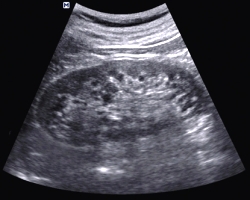

Исследование безболезненное и не имеет противопоказаний. Ультразвуковая диагностика выполняется в положении лежа на боку и спине. Для исключения нефроптоза врач дополняет исследование сканированием в положении стоя или сидя.